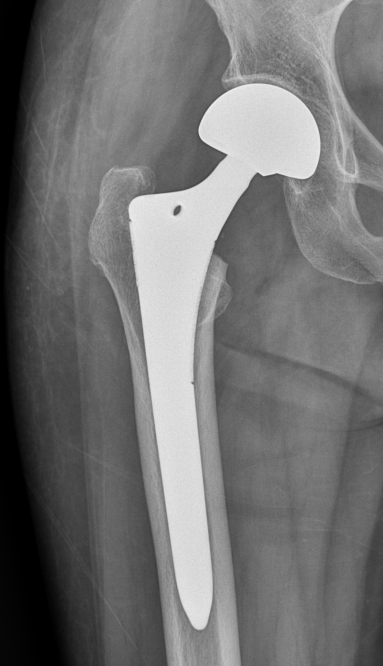

- BPHA는 비구(Acetabulum)를 그대로 두고, 대퇴골두(Femoral Head)만 인공관절(대퇴주대)로 치환하는 수술이다.

대퇴골두를 제거하고 금속 대퇴 주대(Stem)를 대퇴 골수강에 시멘트로 충전하거나 시멘트 없이 단단히 끼워넣어 고정한다.